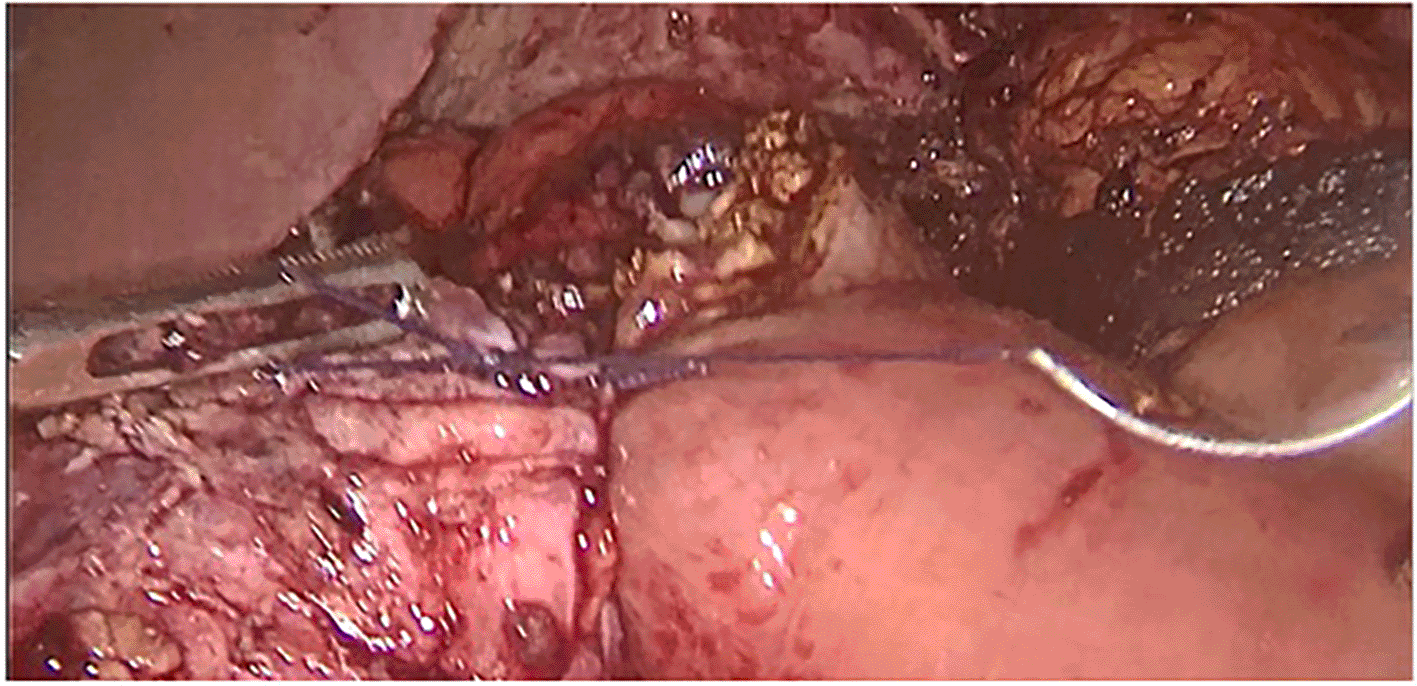

Surgery was then performed. After pneumoperitoneum was established using Hasson technique, dense adhesions between the gastric tube, the left hepatic lobe, and the left diaphragm were freed; using scissors to avoid energy related injuries. Peri-fistular fibrosclerosis made the dissection taut and hemorrhagic (Figure 1). There was a fistulous tract on the anterior aspect of the gastric pouch measuring 1 cm in diameter with hardened edges. To achieve tension-free fistula-jejunal anastomosis, the intra thoracic esophagus was freed (Figures 2 and 3). A jejunal loop, 60 cm from the ligament of Treitz, was raised and anastomosed manually in a termino-lateral fashion; with a running 4-0 vicryl thread (Figures 4 and 5). Surgical intervention was completed by drainage of the hiatal orifice. Our patient was discharged on the 10th POD and has remained well since then. Five years later, the patient did not report dysphagia or cough, and had a stable BMI.

3333b6e2-f1ad-4796-b1c5-60092c71668b_figure2.gif

Figure 2. Intra thoracic dissection of gastric pouch.

3333b6e2-f1ad-4796-b1c5-60092c71668b_figure3.gif

Figure 3. Lowering the mediastinal esophagus.